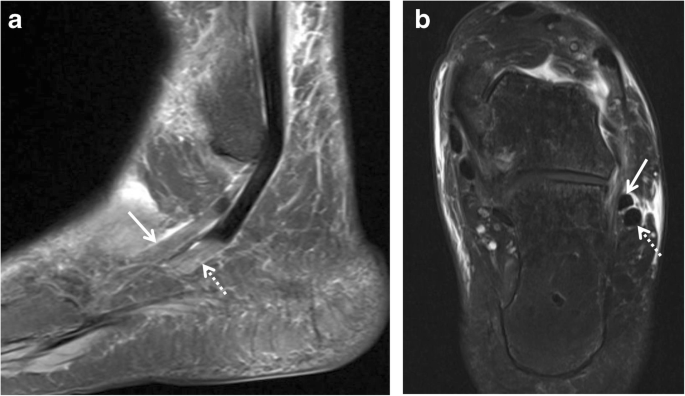

Peroneal Tendon Dislocation And Superior Peroneal Retinaculum Injury Radsource - Two papers have reported mri of peroneal tendon splits.7, 8 it is useful for differentiating peroneal tendon splits from other lateral ankle disorders.

The Peroneus Longus Muscle And Tendon A Review Of Its Anatomy And Pathology Springerlink - Magnetic resonance imaging (mri) is the criterion standard for identifying peroneal tendon injuries, which are surgery is indicated in the acute phase for peroneus brevis tendon rupture, acute dislocation, and anomalous peroneal brevis muscle hypertrophy and for peroneus longus tears that.